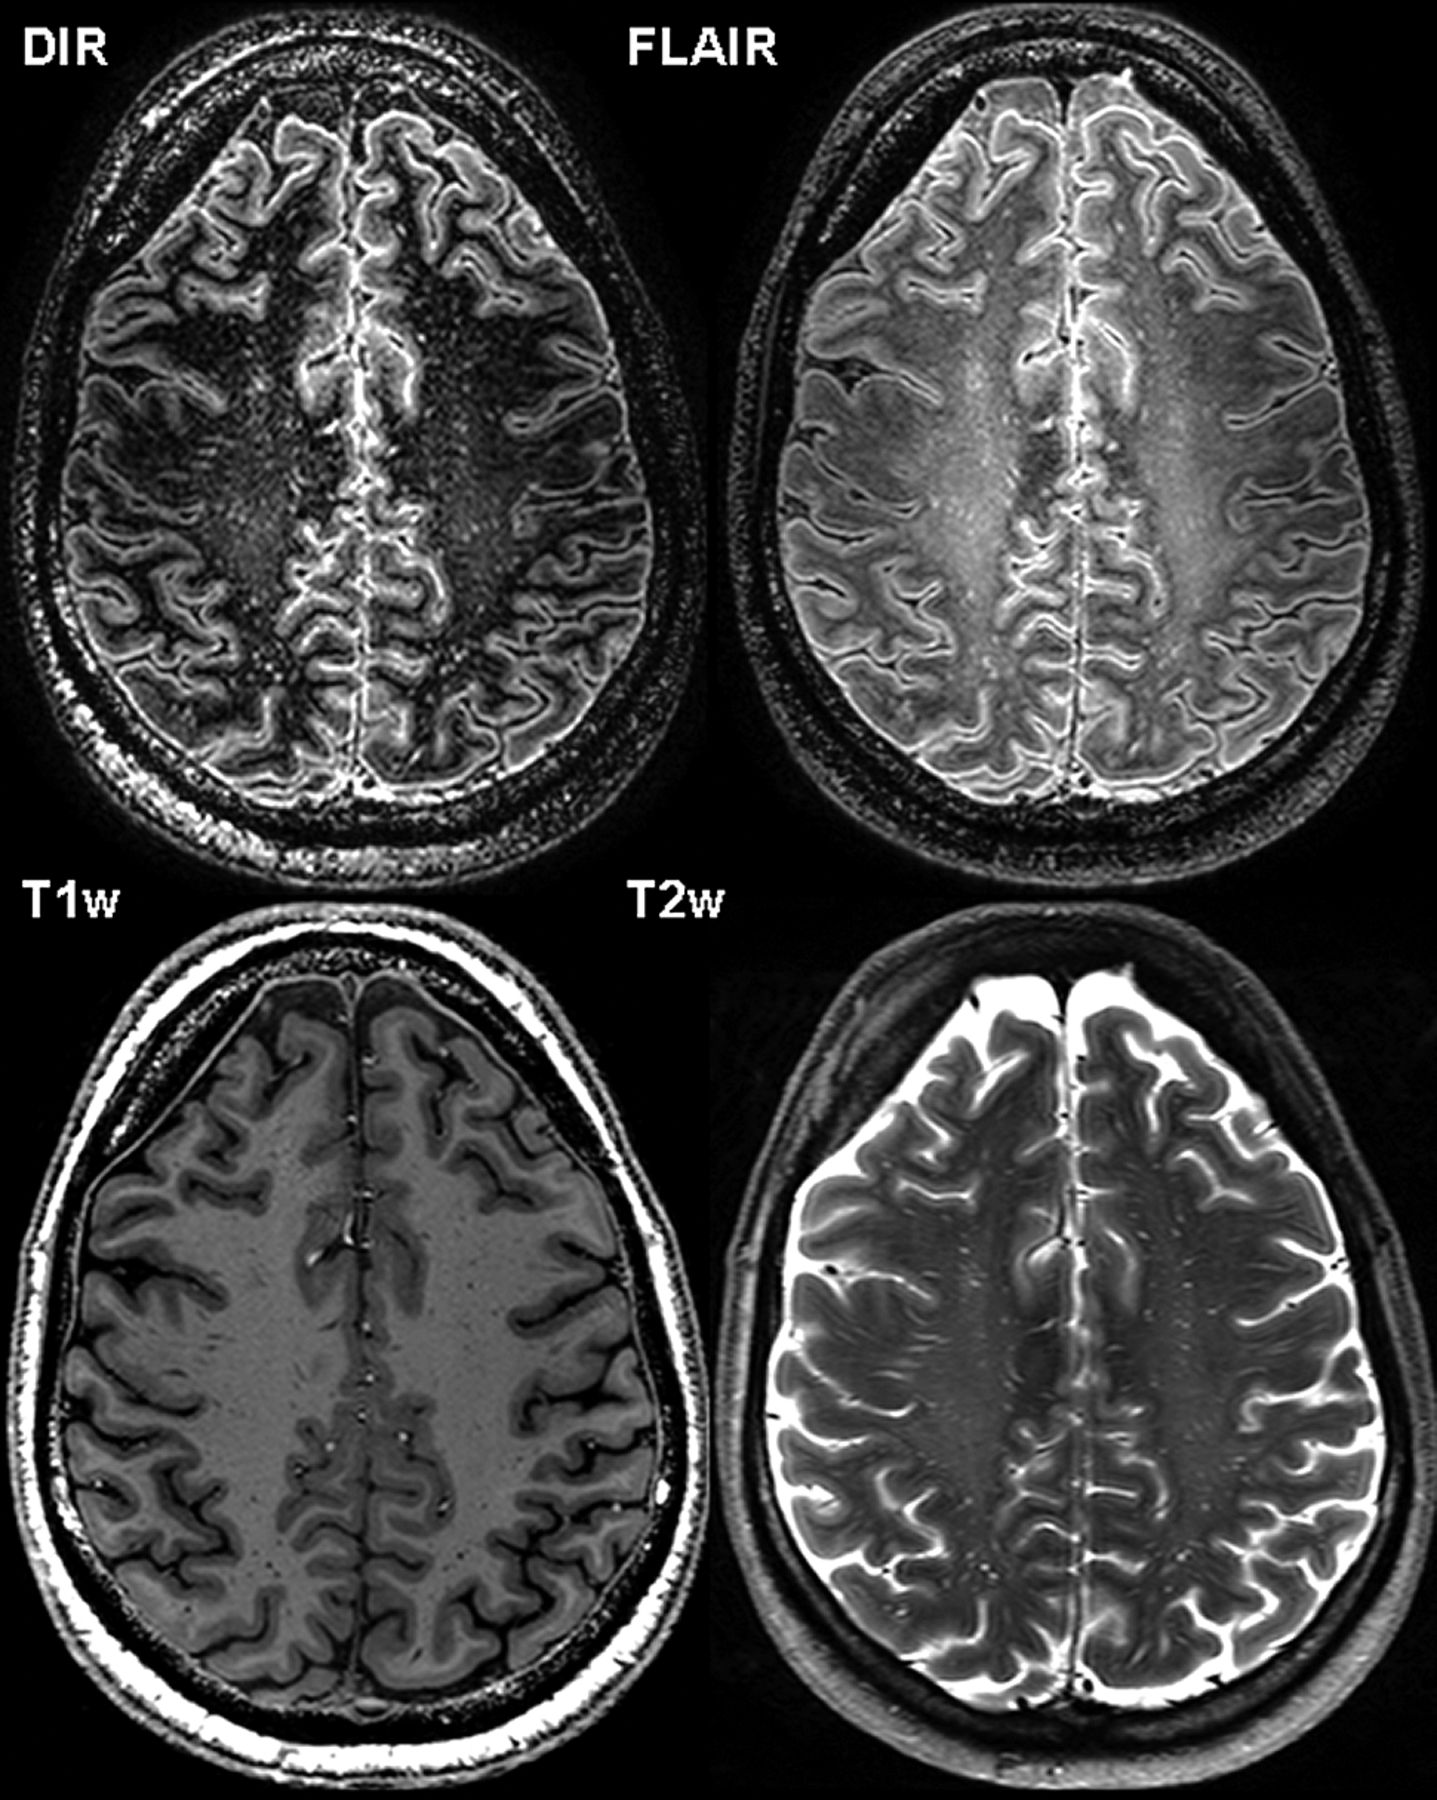

In the healthy control subjects, 40 lesions were found on the 3D-FLAIR images, 26 on 3D-DIR, 24 on 2D-T2WI, and 21 on 3D-T1WI. Of these lesions, 79% were periventricular and deep white matter lesions, presumably of vascular ischemic origin. No intracortical lesions were identified in any of the healthy control subjects; only 1 mixed lesion was found in 1 healthy control on 3D-DIR. An example of the 7T sequences in a healthy control subject can be found in Fig 1.

Axial 3D-DIR, 3D-FLAIR, 3D-T1WI, and 2D-T2WI at 7T MR imaging of a 50-year-old healthy male control. Note the hyperintense visualization of both the outer (subpial) layers of the cortex and perivascular spaces on both 3D-DIR and 3D-FLAIR images.